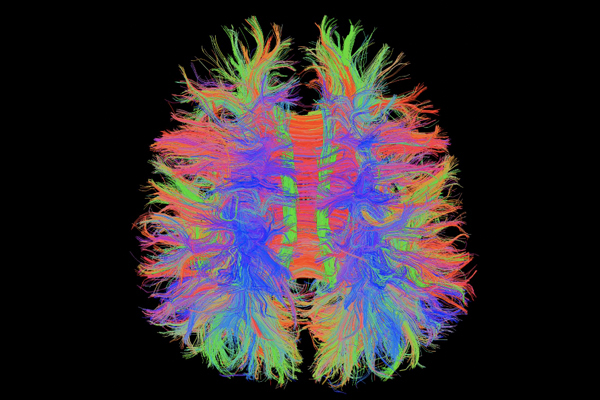

Chẩn đoán toàn thân: đầu, cổ, cột sống, khớp, bụng, tiểu khung, mạch máu

Phù hợp với nghiên cứu và workflow thông minh nhờ kết nối từ xa, các chuỗi quét tiên tiến và xử lý ảnh cao cấp